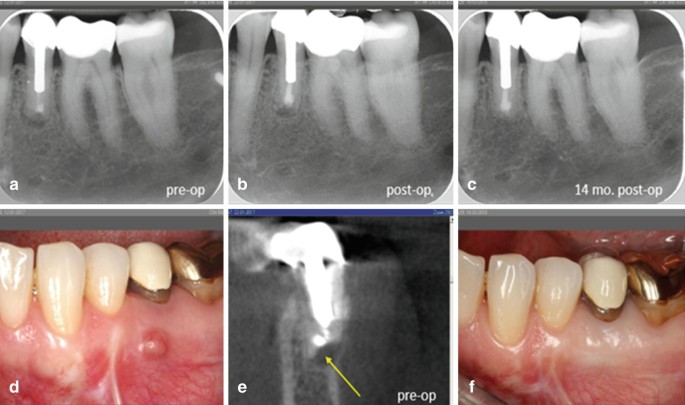

Endodontic Considerations In The Management Of Endodontic Periodontal Lesions Springerlink